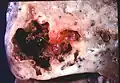

L'abcès pulmonaire est un type de nécrose liquéfiée du tissu pulmonaire et la formation de cavités (plus de 2 cm)[1] contenant des débris nécrotiques ou du liquide, causée par une infection microbienne.

Image de pathologie d'un abcès pulmonaire.